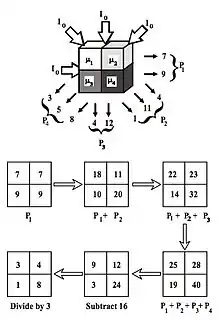

- A basic premise in back-projection is that any attenuation of the X-ray beam has occurred uniformly along the path followed from the source to the detector. Let's consider a simple tomographic slice containing just four voxels to illustrate the computational approach - see Figure 7.11. The first projection, P1 is obtained from a horizontal exposure from left to right in the figure. The back-projection of P1 involves putting the values 7 and 9 in both elements of the first and second rows, respectively. The second projection, P2 adds a 4 to the top right element, 1 to the bottom left element and 11 to the other two elements when it is back-projected. The other projections are treated in a similar fashion. Following regularisation of the data set the final image is obtained at the bottom left of the figure.

- The reconstruction process is illustrated in Figure 7.15.12 for a simple image consisting of a 2x2 pixel matrix. It starts with a guess of a solution and then compares the actual projections with the ones obtained on the basis of the guess. Modifications are made to the pixel values and the procedure is repeated. Repetitive iterations are made until the differences between the measured and calculated projections are insignificant.

- The first estimate of the image matrix is made by distributing the first projection, P1, evenly through an empty pixel matrix. The second projection, P2, is then compared to the same projection from the estimated matrix and the difference between actual and estimated projections is added to the estimated matrix. The process is repeated for all other projections.